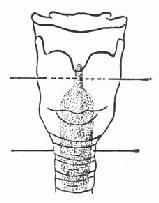

(2)急性声门损伤:急性声门损伤表现甲状软骨骨折和声带粘膜裂伤(图96-5、6)。需在局麻下行常规气管切开术。直接喉镜的检查可进一步明确喉粘膜破裂的部位及程度,声门损伤检查可见声带及前连合粘膜裂口及肿胀。

图96-5 甲状软骨骨折

图96-6 声带粘膜裂伤